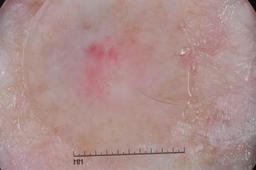

{

"acquisition_day": 1070,

"age_approx": 75,

"anatom_site_general": "upper extremity",

"concomitant_biopsy": true,

"diagnosis_1": "Benign",

"diagnosis_2": "Flat melanotic pigmentations - not melanocytic nevus",

"diagnosis_3": "Lentigo NOS",

"diagnosis_confirm_type": "histopathology",

"image_manipulation": "instrument only",

"image_type": "dermoscopic",

"lesion_id": "IL_2952637",

"melanocytic": true,

"patient_id": "IP_1039004",

"sex": "female"

}